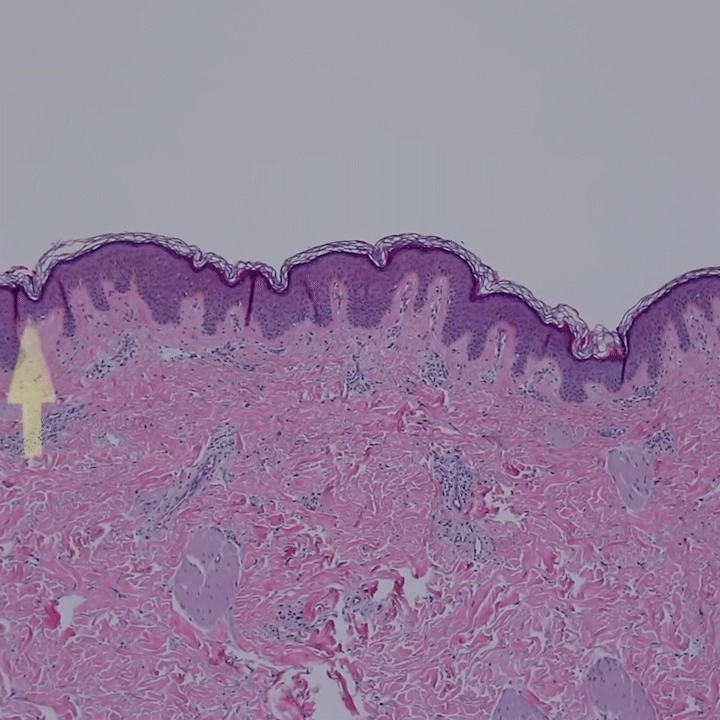

无毛皮肤表皮层的显微和超微结构

病理学切片,鳞状上皮化生

我们将从医学切片的角度来详细认知一下真实的皮肤结构和功能,为我们